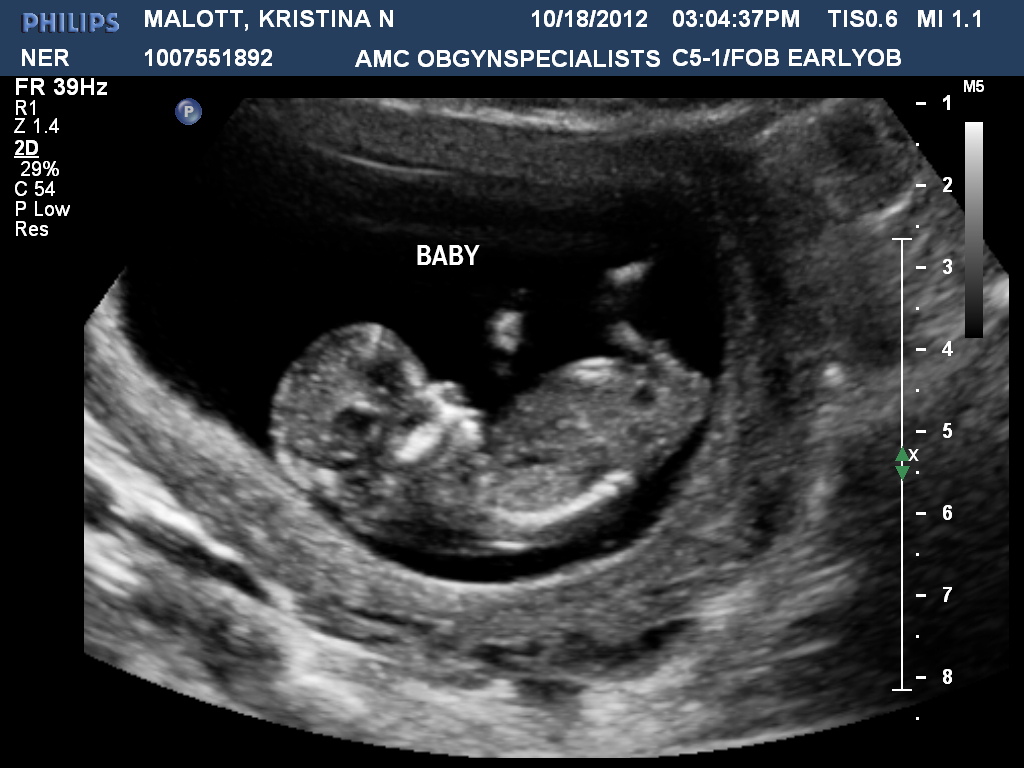

Attachment 5819Attachment 5820

Anyone?? I am kinda confused by this any help would be awesome!!! Thanks!

I'd say that the forky thing is a girl nub; a) because most of the forky-looking nubs are girls and b) the nub is lying stright.

i can't see clear nub

Maybe a girl but it's hard to be sure I'm looking at the nub right.

Looks like a girl in the second pic! I don't see anything in the first